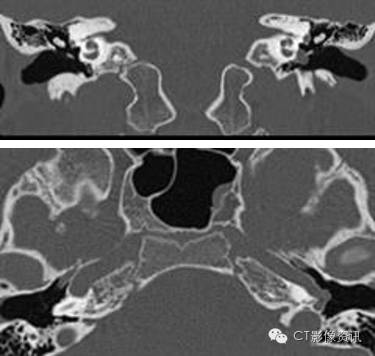

检查所见 CT图像显示明显异常,尽管所示两种异常罕见,但是该异常经常伴随发生。 首先,岩段水平部颈动脉管延长,岩段垂直部缺失。颈动脉自下方扩大的鼓室管进入并穿行中耳。鼓室段颈动脉没有骨质覆盖,并且紧贴鼓膜和听骨链。横断位图像显示出颈动脉狭窄的典型表现。 其次,起源于上颌动脉下颌支的脑膜中动脉需要穿行进入颅内硬膜外间隙的棘孔缺如。而棘孔缺如或者发育不良和第二个诊断直接相关。对CT图像进一步观察发现一个明显的软组织隆起,与右侧不对称,该隆起所在位置恰为面神经走行路径。耳蜗岬细微的侵蚀是该类病变另一种少见的异常,并且由此可能会导致感音神经性耳聋。

最终诊断:颈内动脉变异(左侧)并永存镫骨动脉